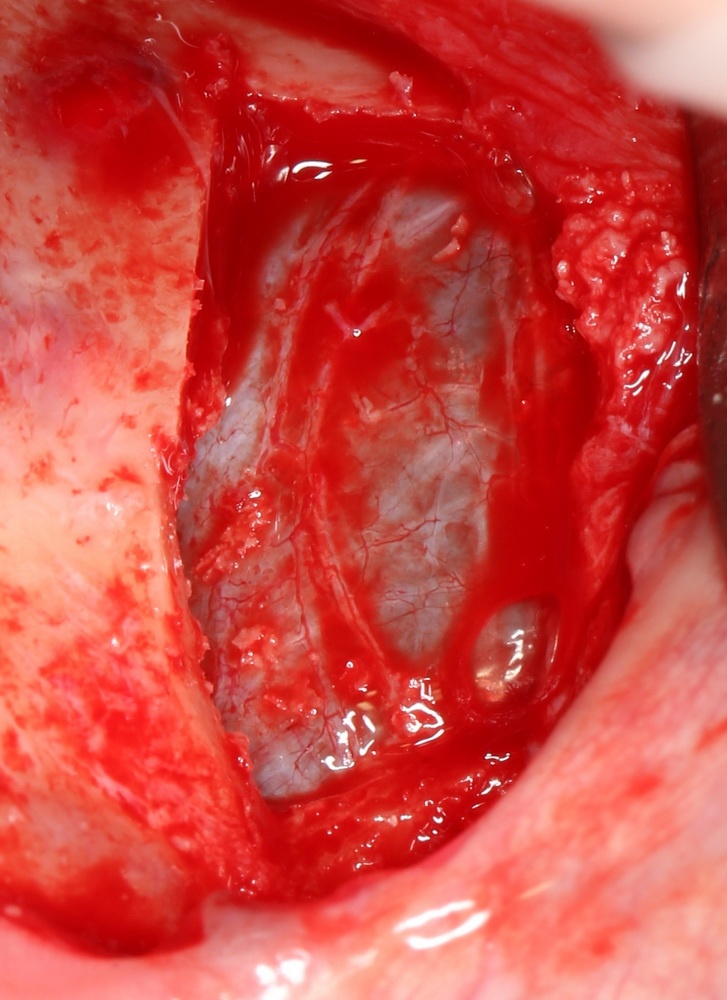

Самый известный способ проверить, есть ли повреждения слизистой оболочки верхнечелюстной пазухи — это попросить пациента глубоко вдохнуть и выдохнуть. При этом, шнайдерова мембрана будет двигаться:

На вдохе втягиваться внутрь:

На выдохе — выпирать:

Если она не двигается, если из субантральной полости идут пузыри — это верный признак, что где-то слизистая оболочка повреждена.

Однако, данный тест не дает гарантии, что перфорации нет. Небольшая перфорация может быстро закрыться кровяным сгустком, у пациента может быть просто заложен нос и т. д. — поэтому полностью полагаться на него нельзя.